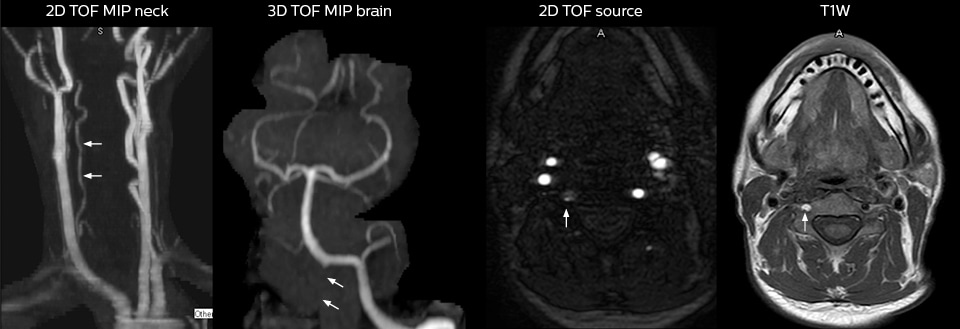

This patient presented with headache that was worse with neck flexion and we see a Chiari 1 malformation with low-lying cerebellar tonsils as well as some degenerative cervical thrombolytic change.